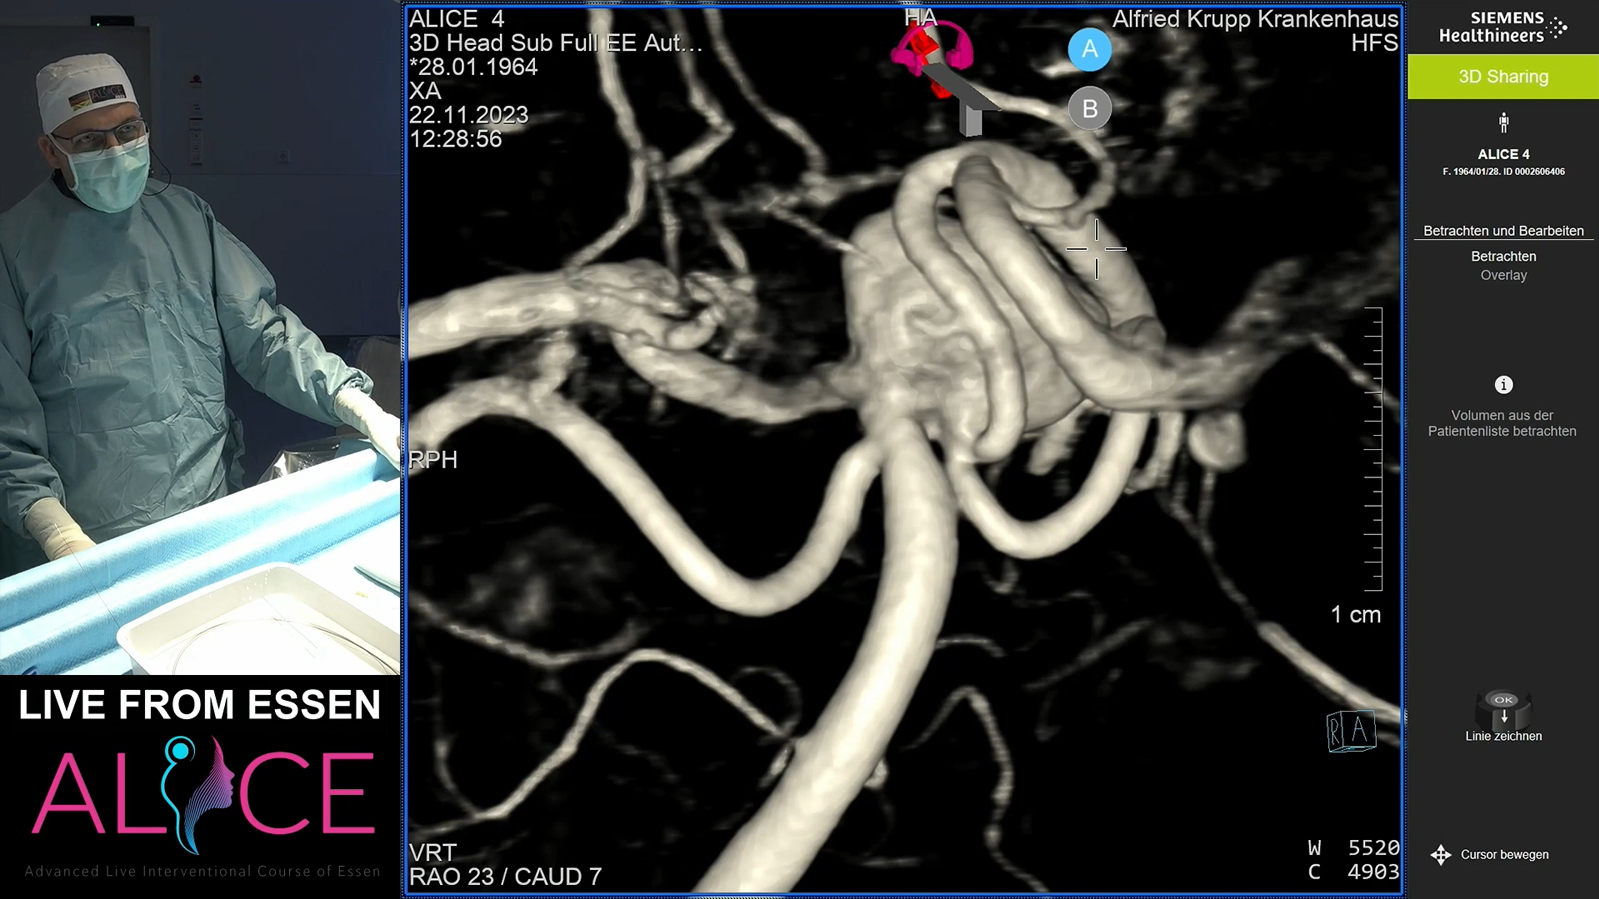

Essen: M1 stenosis with ICA tonsillar loop